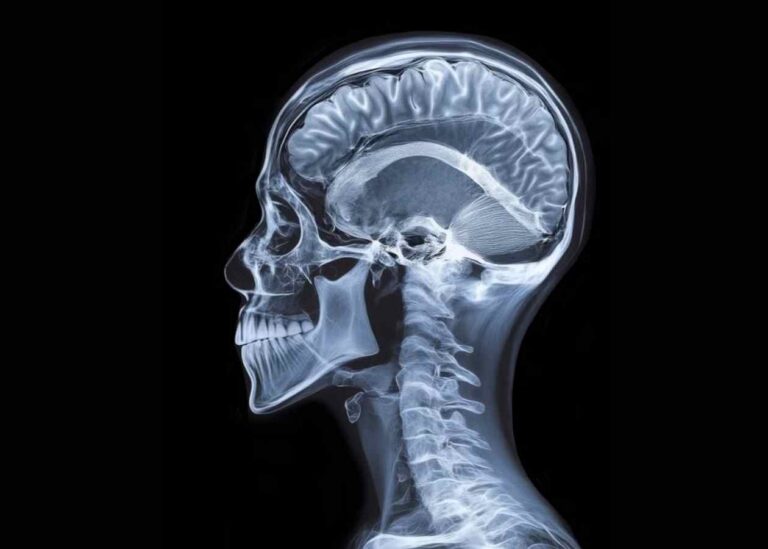

Tam Kapalı (Full Endoskopik) Boyun Fıtığı Ameliyatı Nedir? Avantajları Nelerdir?

Boyun fıtığı, özellikle masa başı çalışanlar, uzun süre telefon ve bilgisayar kullananlar ile duruş bozukluğu olan…